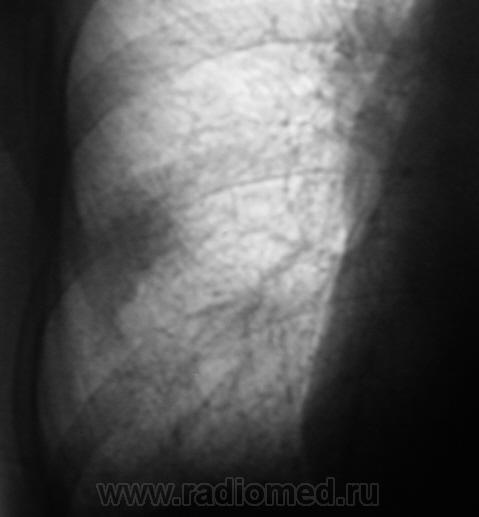

Флюорограмма за 2009 г.